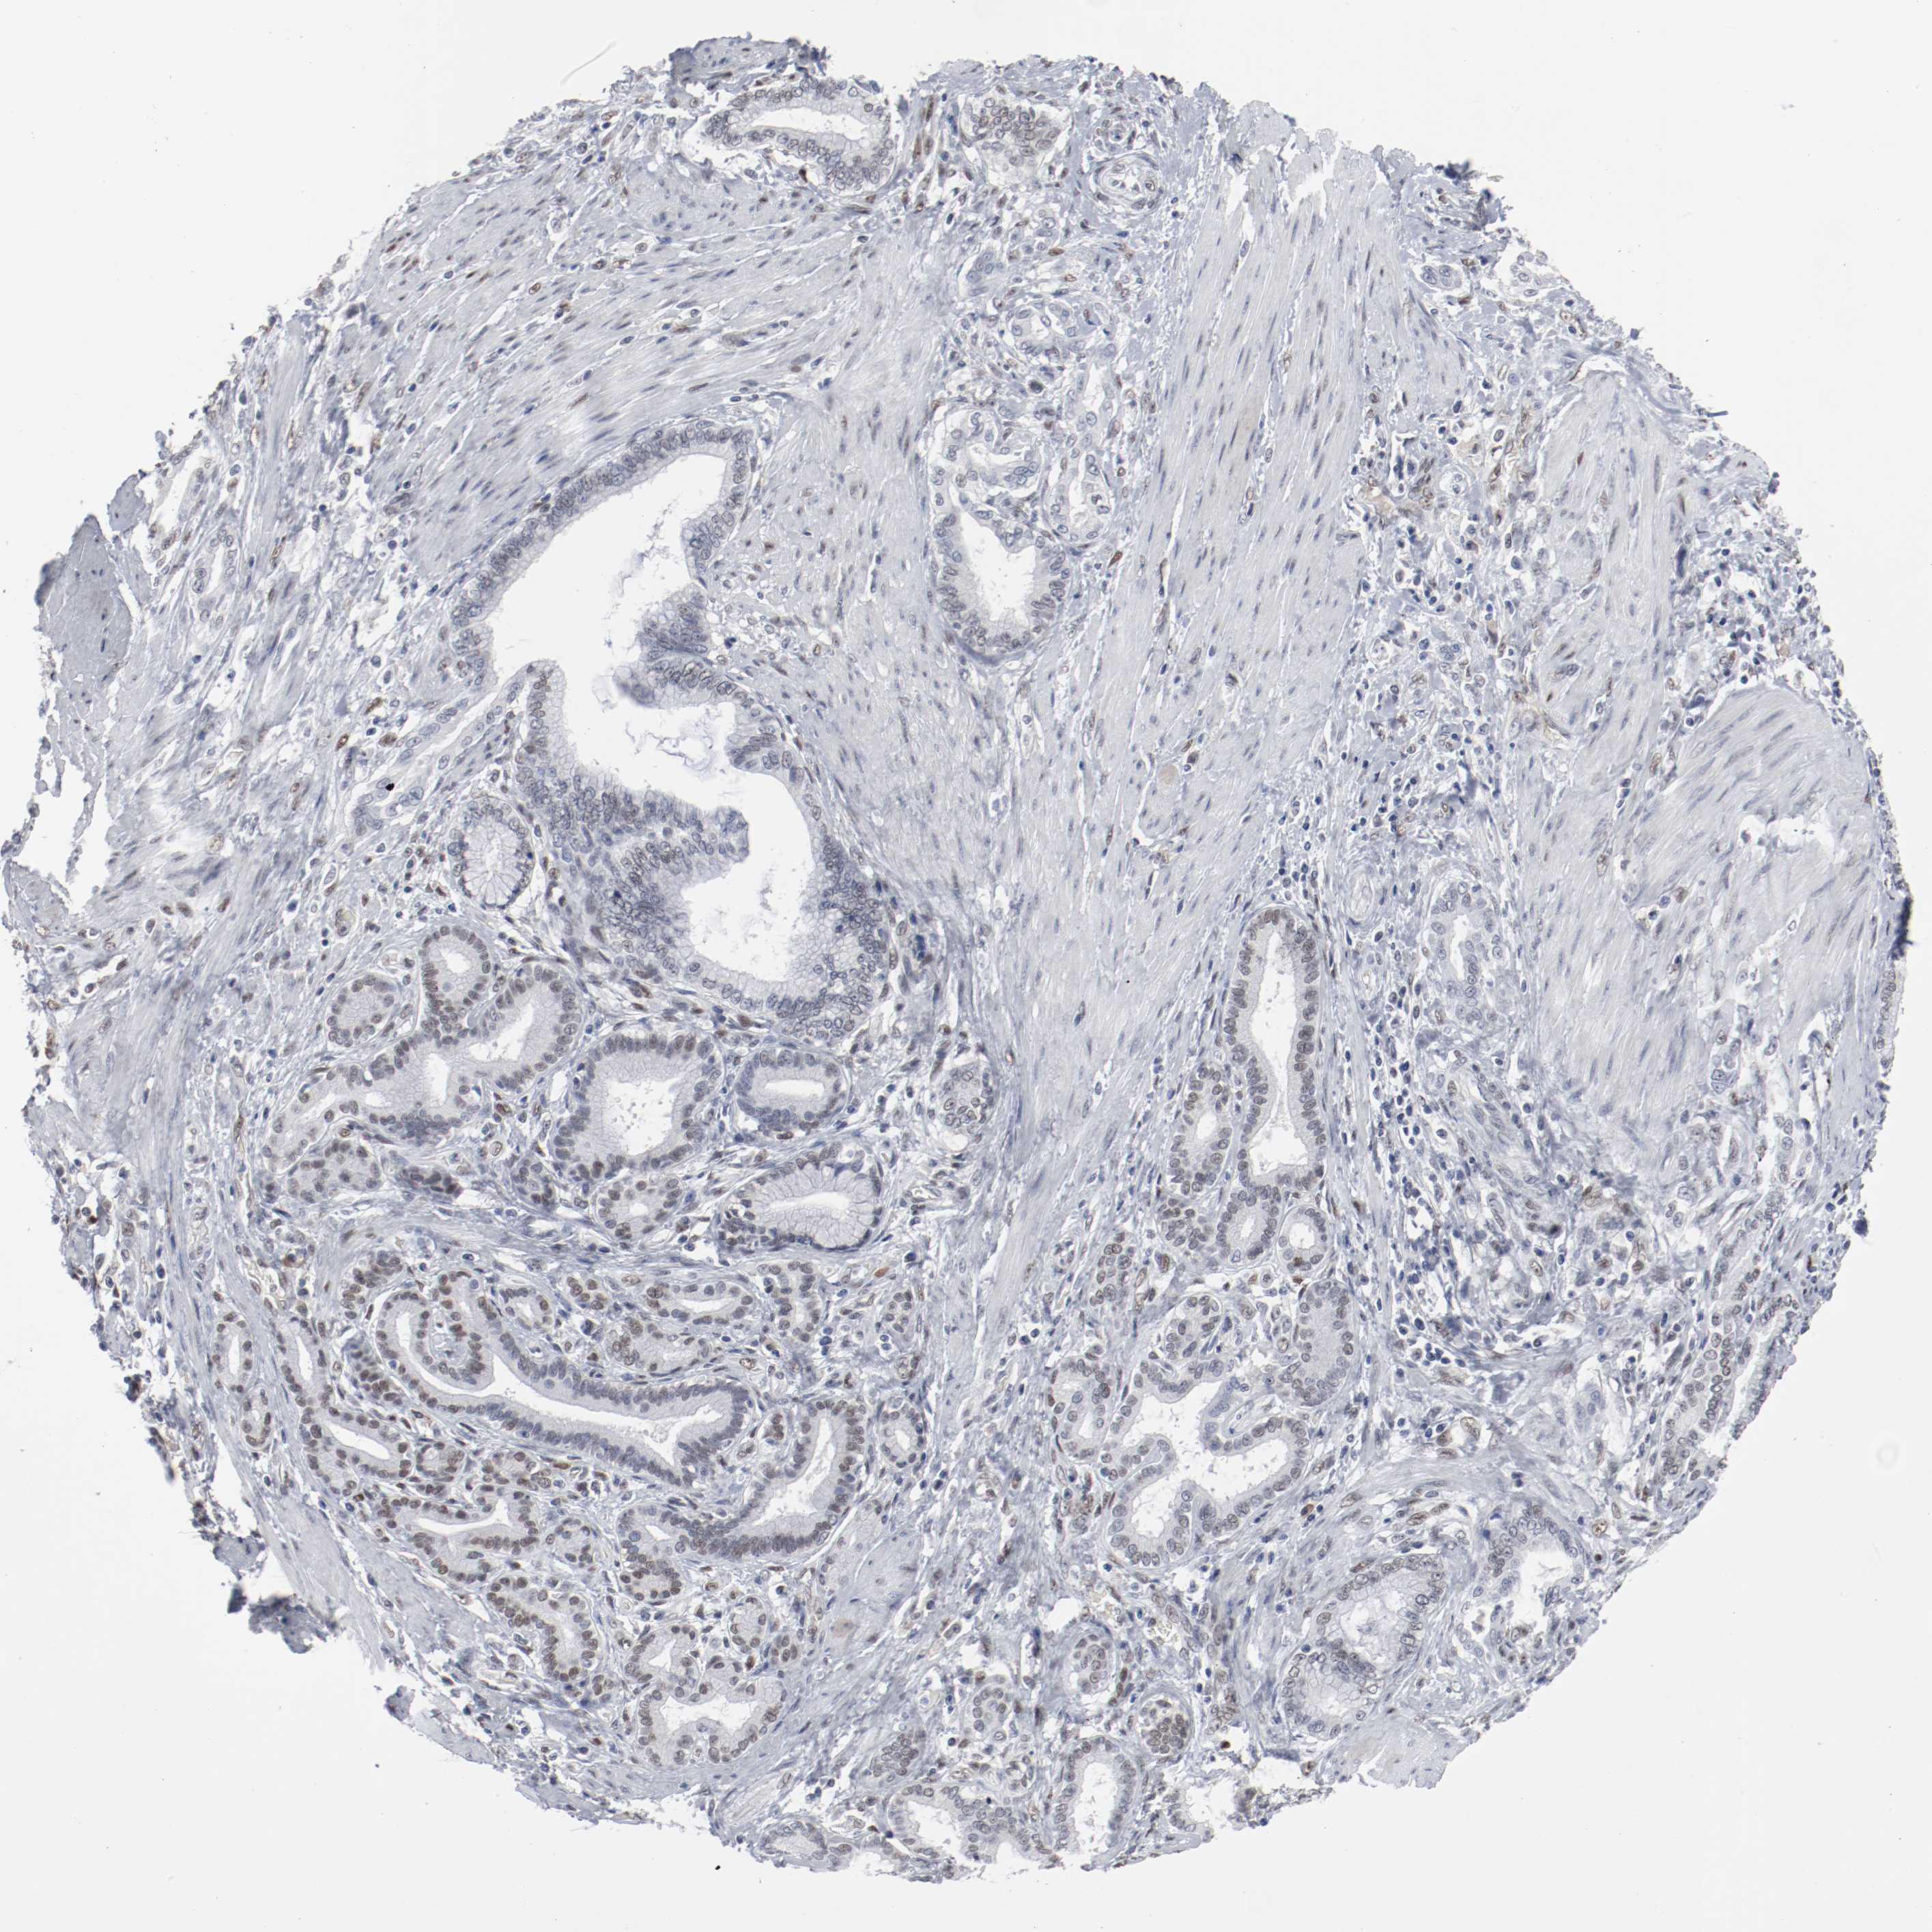

PANCREATIC CANCER - Protein expressioni

A mouse-over function shows sample information and annotation data. Click on an image to view it in a full screen mode. Samples can be filtered based on level of antibody staining by selecting one or several of the following categories: high, medium, low and not detected. The assay and annotation is described here.

Note that samples used for immunohistochemistry by the Human Protein Atlas do not correspond to samples in the TCGA dataset.

Antibody stainingi

Antibody staining in the annotated cell types in the current human tissue is reported as not detected, low, medium, or high, based on conventional immunohistochemistry profiling in selected tissues. This score is based on the combination of the staining intensity and fraction of stained cells.

Each image is clickable and will lead to virtual microscopy that enables deeper exploration of all samples and also displays staining intensity scores, fraction scores and subcellular localization as well as patient and tissue information for each sample.

Antibody HPA003384

Staining

High

Medium

Low

Not detected

Intensity

Strong

Moderate

Weak

Negative

Quantity

>75%

75%-25%

<25%

None

Location

Nuclear

Cytoplasmic/membranous

Cytoplasmic/membranous,nuclear

Adenocarcinoma, NOS

Adenocarcinoma, metastatic, NOS